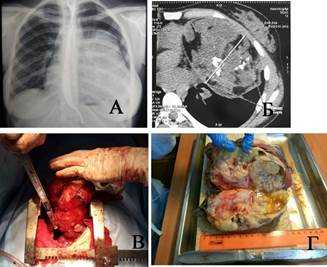

Наблюдение 1. Женщина 18 лет. Студентка. Жалоб не предъявляет. При флюорографии и последующей КТ определяется массивное затемнение, исходящее из переднего средостения, пролабирующее в левую плевральную полость (рис. 1а). Средостение смещено вправо. Структура опухоли неоднородна: видны множественные костно-хрящевые включения и кистозные участки (рис. 1б). Операция: полная продольная стернотомия. Опухоль отделена от грудной стенки. Верхняя доля левого легкого в ателектазе. От легкого опухоль отделена швом аппарата ТА-60. Ножка опухоли исходит из переднего средостения и также пересечена после прошивания ТА-60 (рис. 1в). Продолжительность операции 2 часа 15 минут, кровопотеря 530 мл. Гистологически: зрелая тератома (рис. 1г). Послеоперационный период гладкий. Контрольный осмотр через 2 года - здорова.

Рис. 1. Наблюдение 1: а) обзорная рентгенограмма пациентки, б) компьютерная томограмма той же больной, в) полная продольная стернотомия, отсечение ножки опухоли, г) опухоль на разрезе - зрелая тератома